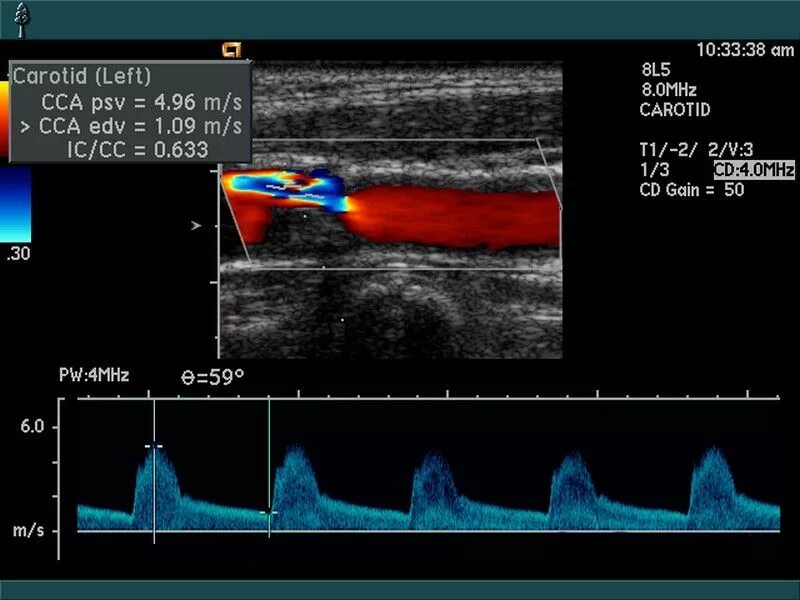

Атеросклеротические изменения брахиоцефальных артерий